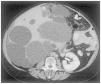

Los quistes se originan como dilataciones focales de los túbulos renales; luego pierden la conexión con éstos. En los estadios iniciales de la enfermedad, el parénquima renal tiene una apariencia relativamente normal. En el estadio terminal, los riñones son muy grandes, presentan innumerables quistes llenos de líquido y contienen tan sólo parches aislados de parénquima relativamente normal rodeado de abundante tejido fibroso (figura 3 A y B). El sistema colector se encuentra habitualmente distorsionado.

Figura 3. Aspecto macroscópico de poliquistosis renal autosómica dominante (PQRAD) vista desde la superficie externa del riñón (A) y corte en el que se ven quistes hepáticos en PQRAD (B).